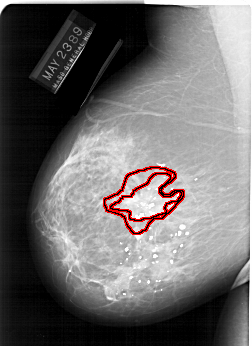

A_1247_1.LEFT_MLO

FILE: A_1247_1.LEFT_MLO.OVERLAY

TOTAL_ABNORMALITIES 1

ABNORMALITY 1

LESION_TYPE MASS SHAPE IRREGULAR MARGINS SPICULATED

ASSESSMENT 5

SUBTLETY 5

PATHOLOGY MALIGNANT

TOTAL_OUTLINES 2

BOUNDARY

CORE